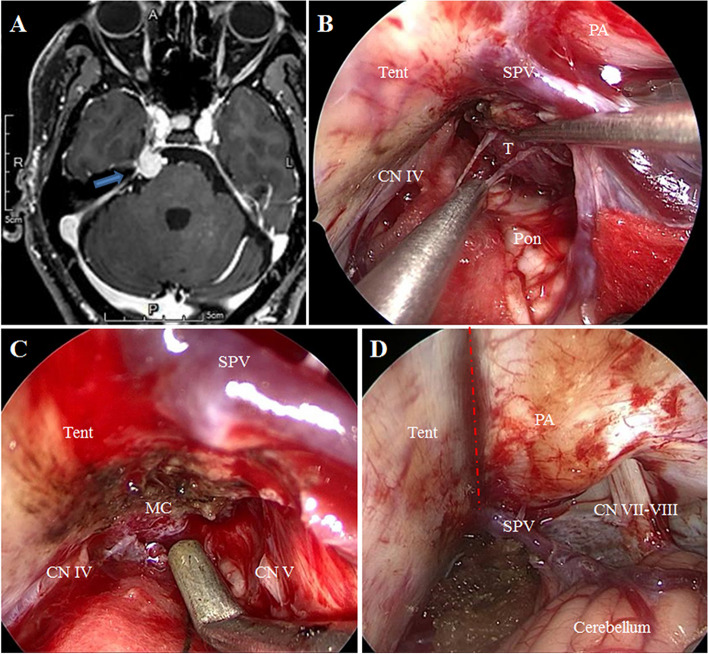

Case presentation: Two patients were presented with severe facial pain and preliminary diagnosis was TN. Preoperative magnetic resonance imaging revealed that a superior cerebellar artery (SCA) compressed the trigeminal nerve in case 1, and a tumor located in the petrous apex extending into the Meckel's cave compressed the trigeminal nerve in case 2. Operations were achieved through the EF-SCITA. The pain was totally relieved with no postsurgical complications in both cases.